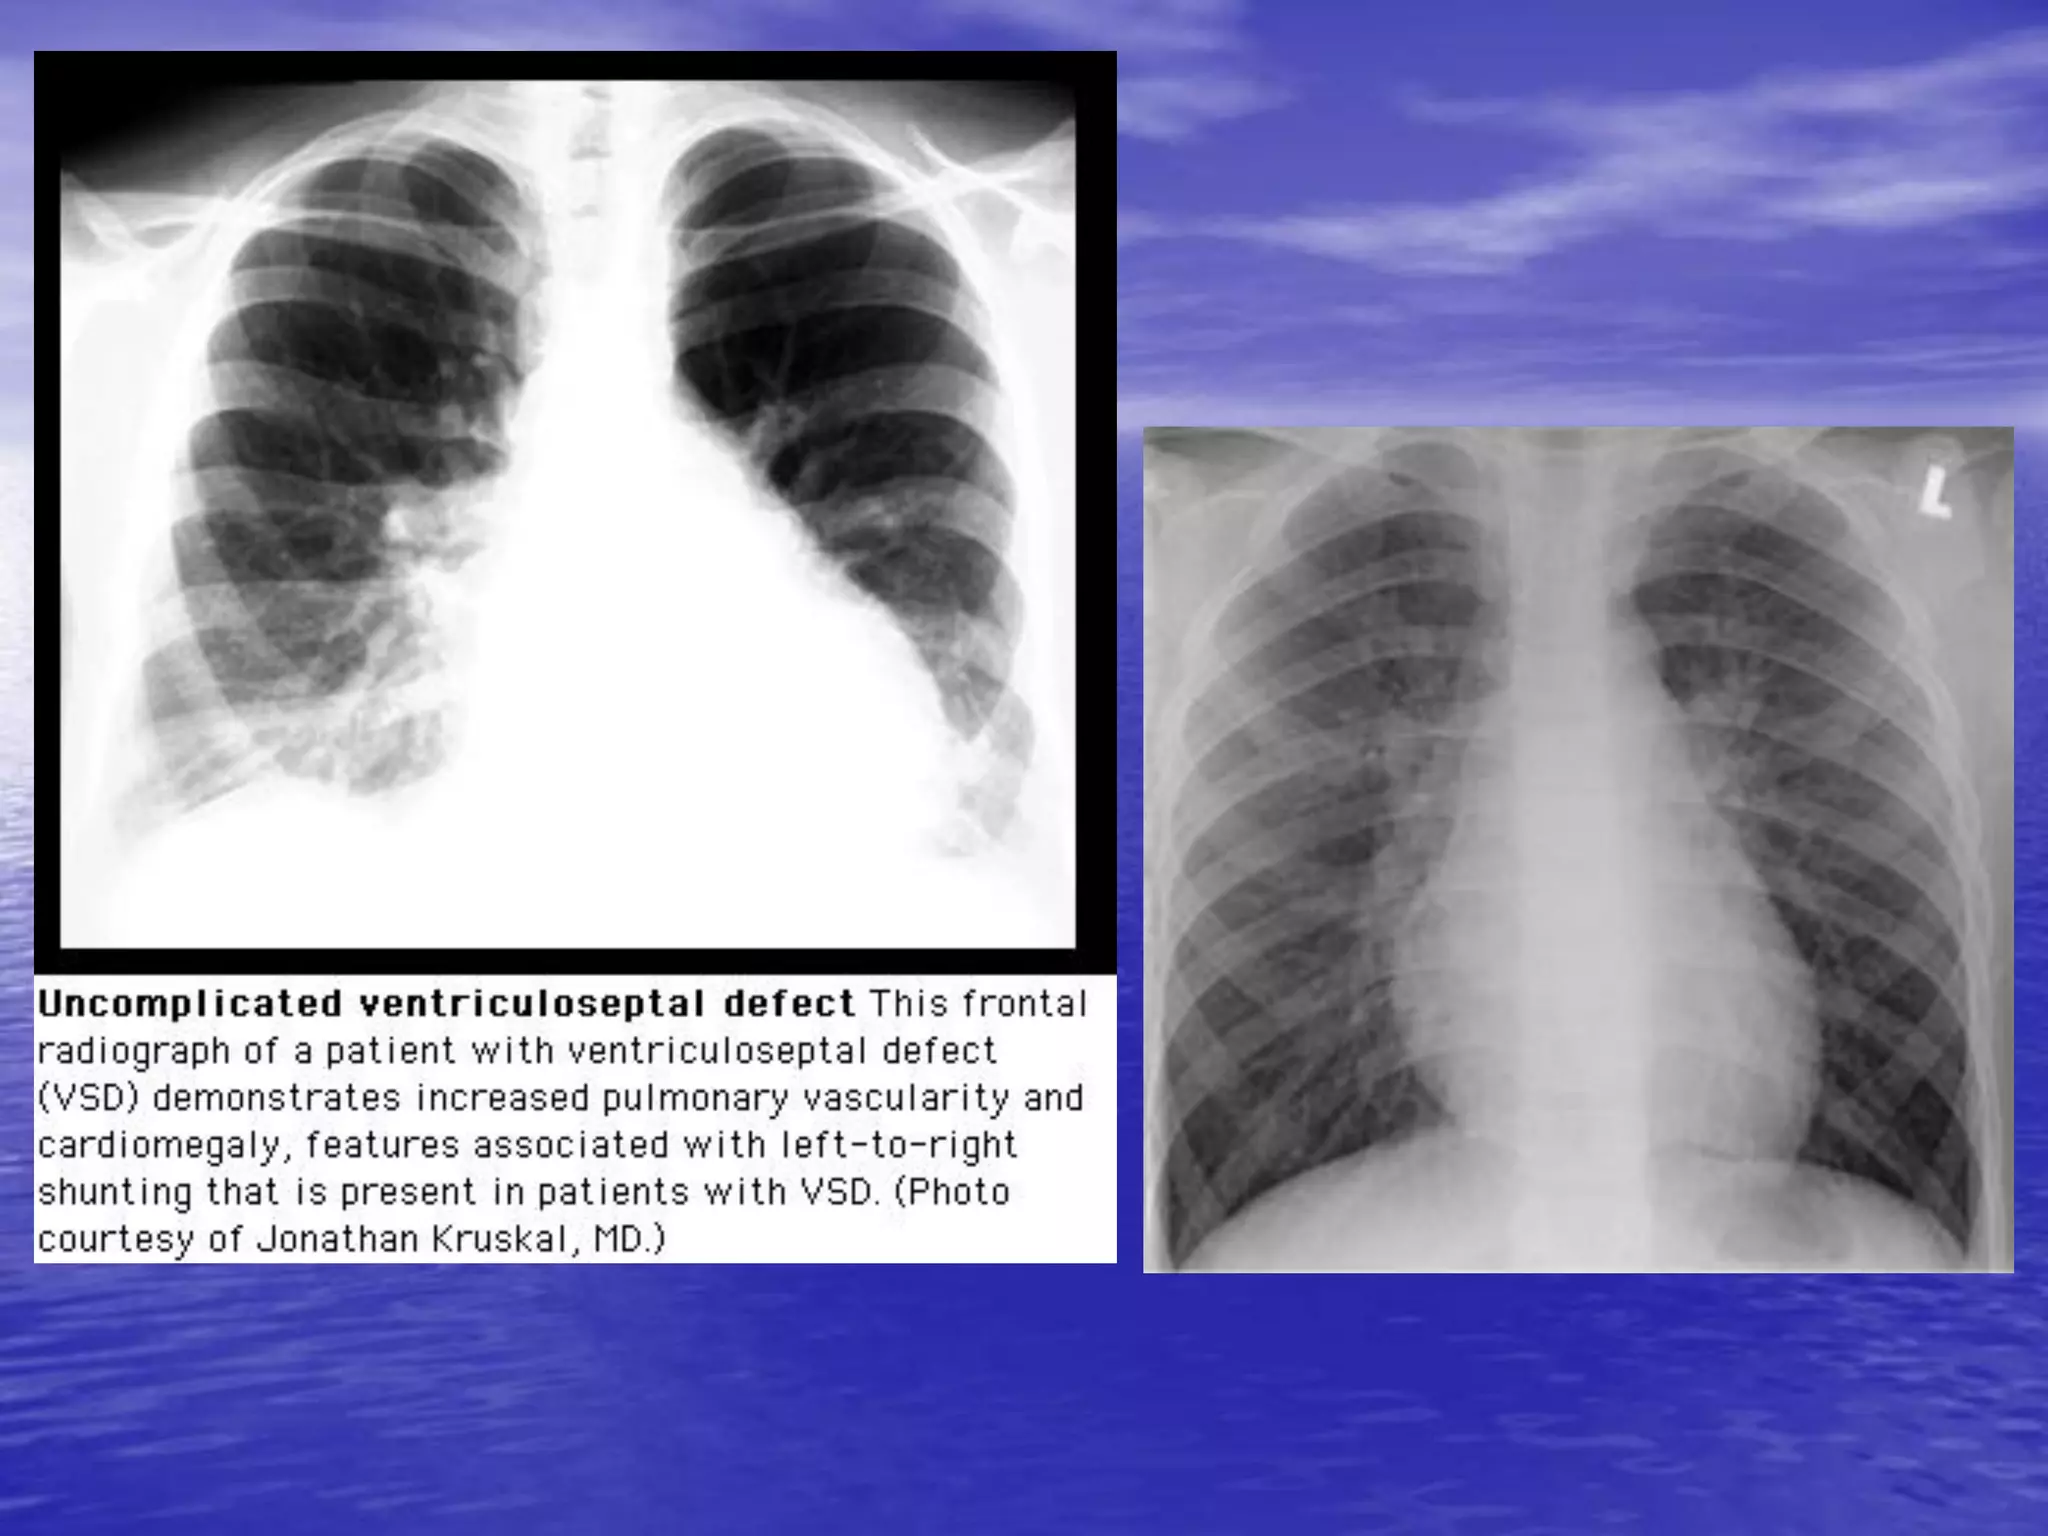

• Tăng tuần hoàn phổi chủ động

– Tăng lưu lượng máu trong ĐMP – tăng tiền mao mạch

phổi

– Nguyên nhân

• Tăng cung lượng tim: sinh lý, bệnh lý

• Tim bẩm sinh: tím, không tím